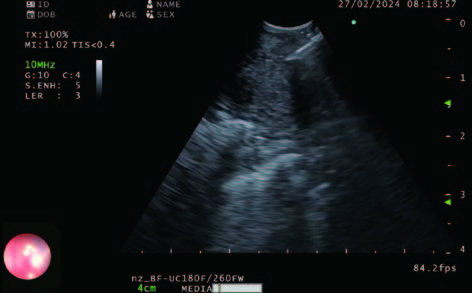

Figure 1 - Lymph node observation with hypoechoic area clearly seen in center of the figure.

B-mode is our go-to mode. This is the basic and most crucial imaging we use for observation of every patient’s node. The improved clarity of B-mode is striking. Lymph nodes are more clearly defined due to better contrast and differences in node consistency is also observed which can help us target different areas of the node to avoid or approach (Figure 1).